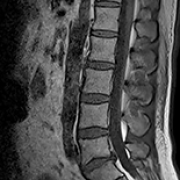

Impact of Lumbar Fusion Internal Fixation on Lumbar Disc Herniation in Young Patients: A Retrospective Study

JiChao Guo, GuoHui Xu

DOI: 10.12659/MSM.944570

Med Sci Monit 2024; 30:e944570

28 Oct 2024 : Clinical Research

JiChao Guo, GuoHui Xu, Sheng Li, ZhiYong Li, JianNing Liu, Wei Wang, XiangBei Qi, WenYuan Ding, Xu Li

3,279